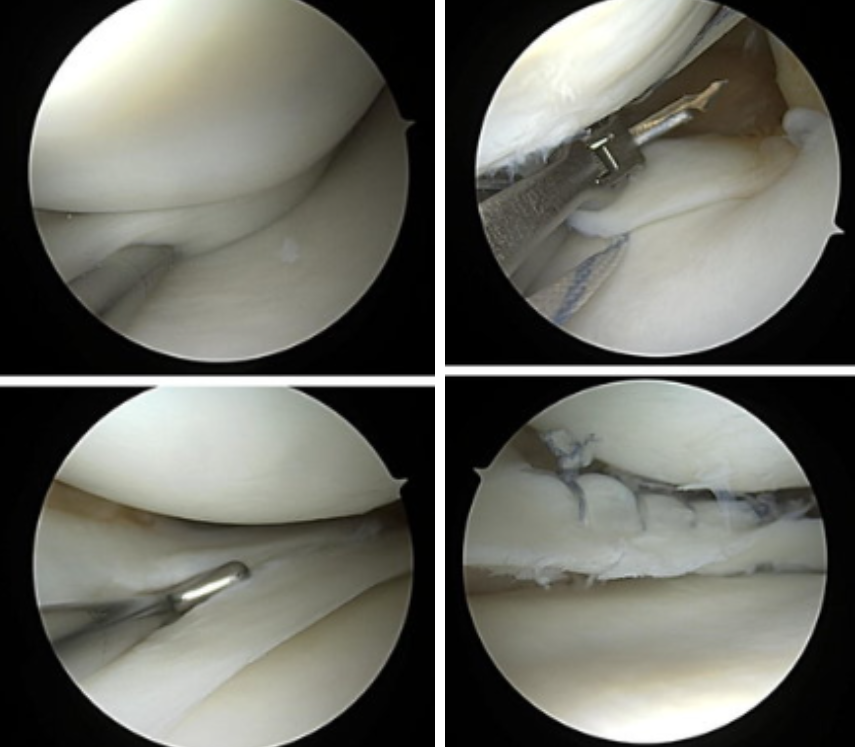

3. 관절경 검사

직접 관절 내시경을 무릎에 삽입해 연골판 손상 부위를 시각적으로 확인하고 동시에 치료(봉합, 절제 등)를 할 수 있는 검사 겸 치료법입니다.

봉합술: 파열 부위가 혈액 공급이 가능한 경우 파열 연골판을 봉합하여 보존하려는 시도

절제술: 재생이 어렵고 봉합이 불가능한 파열 부위는 파열된 연골판을 부분적으로 제거하는 방법